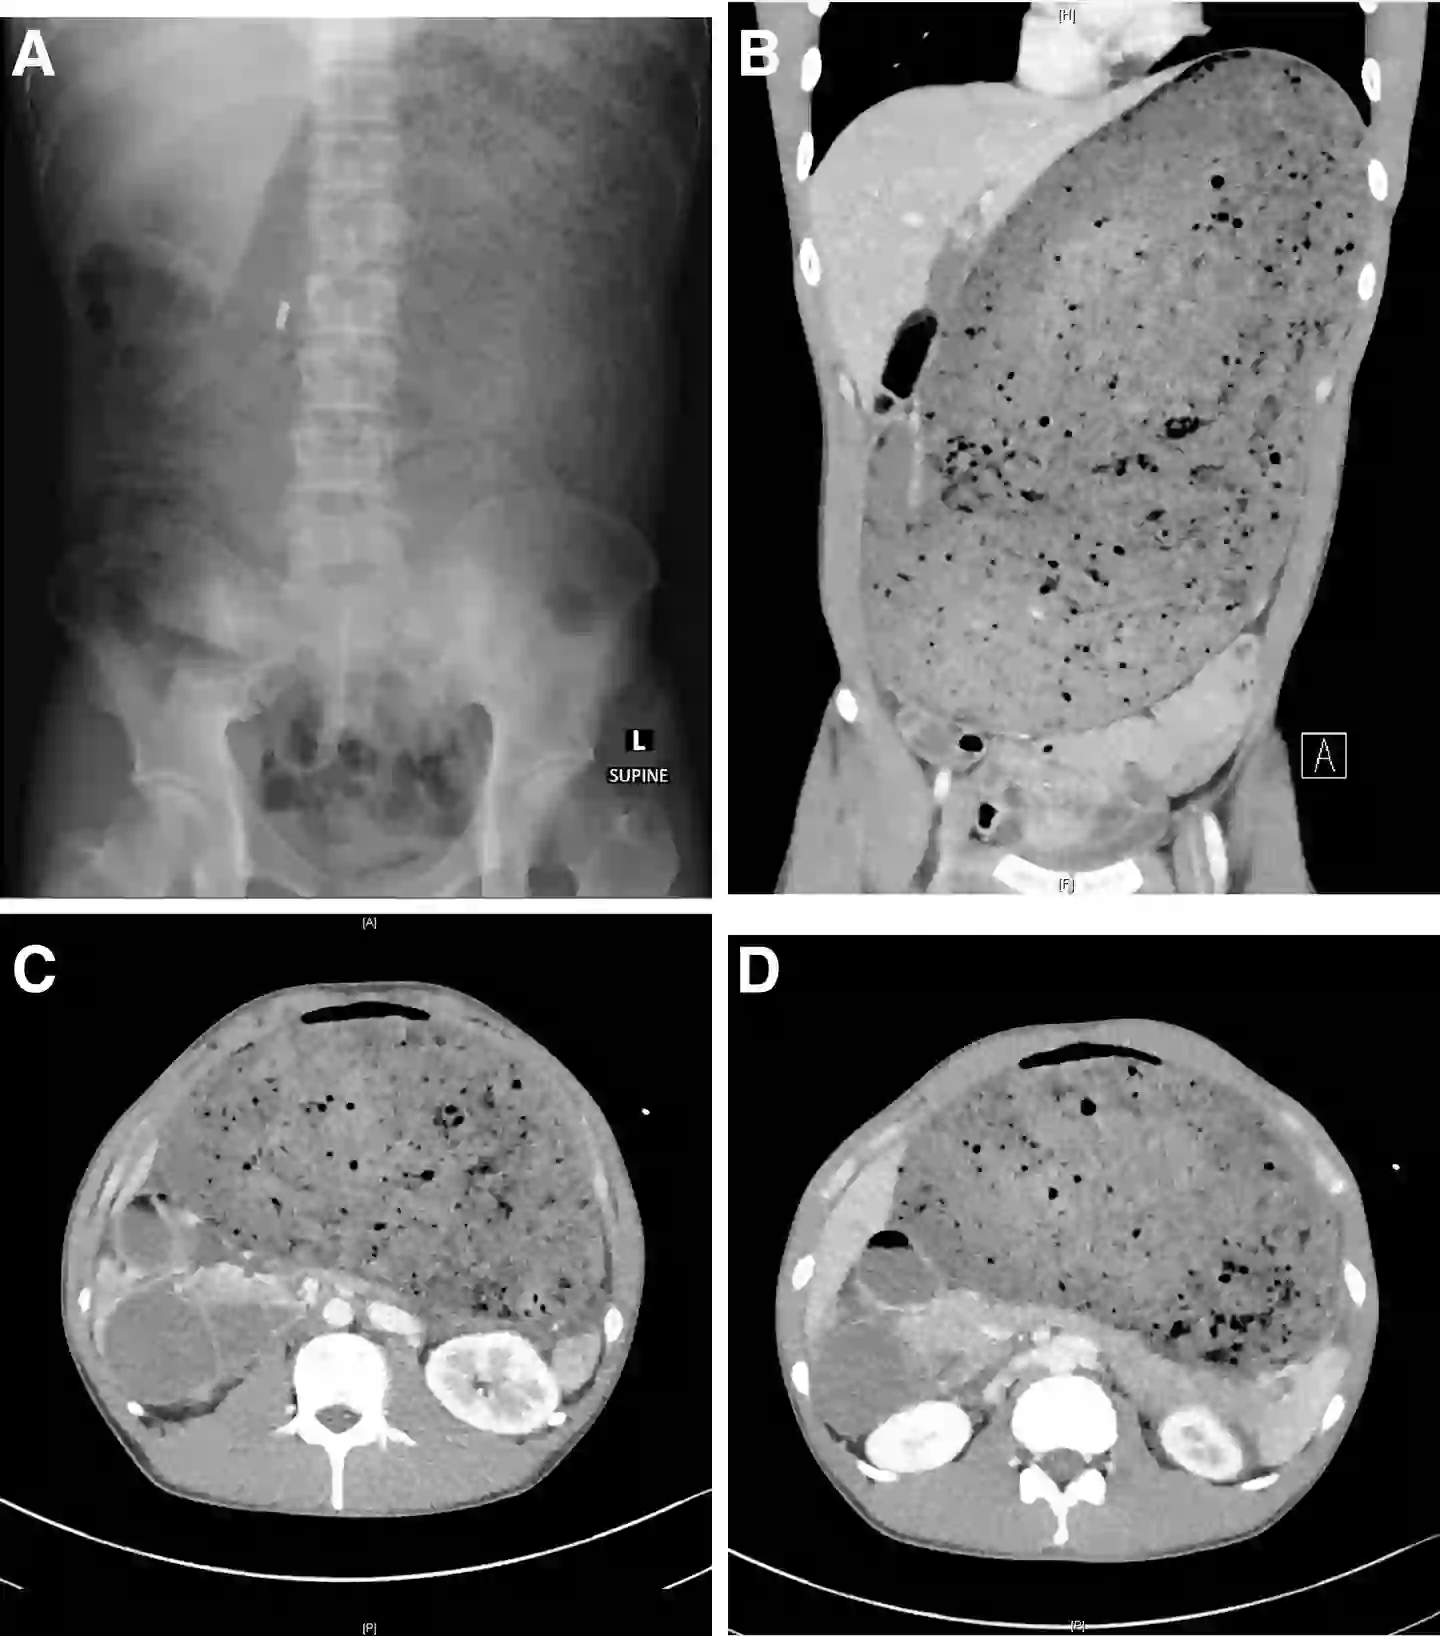

According to the report, published in Gastroenterology aga (American Gastroenterological Association), the man underwent a computed tomography scan of the abdomen and pelvis which detailed the severity of his swollen belly.

It showed his stomach and part of his small intestine were ‘grossly distended with food material’, as well as an abrupt narrowing in another part of the small intestine.

Scans of the man’s distended stomach (Gastroenterology aga)

Meanwhile, ‘the pancreas was compressed’ and the bowels were pushed down.